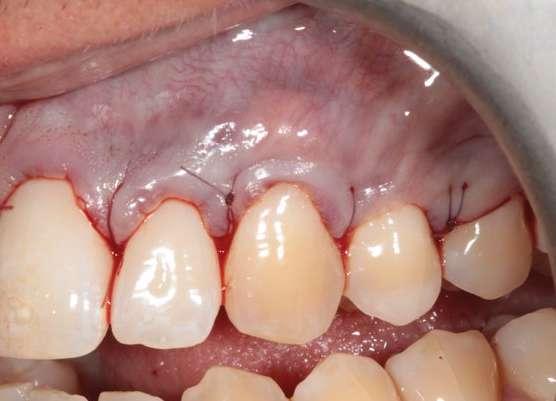

En la exploración clínica observamos recesiones gingivales múltiples en maxilar superior combinado con erosión de la encía y ligero desgaste cervical que borra la línea amelocementaria (Fig. 1). El sondaje periodontal en todos los dientes fue inferior o igual a 3 mm y no se detectaron puntos de sangrado al sondaje. Los dientes 1.3 y 2.3 mostraron ≤ 1 mm de encía queratinizada apical a la recesión. Cabe también destacar la rotación del incisivo lateral superior derecho (1.2). El principal factor etiológico de sospecha en este caso fue el cepillado agresivo.

Figura 1: Situación inicial. Obsérvese la recesión gingival profunda en 1.3 y 2.3, así como la erosión gingival y el borrado de la línea amelocementaria debido al cepillado agresivo.

Figura 3. Situación clínica el día de la intervención quirúrgica.